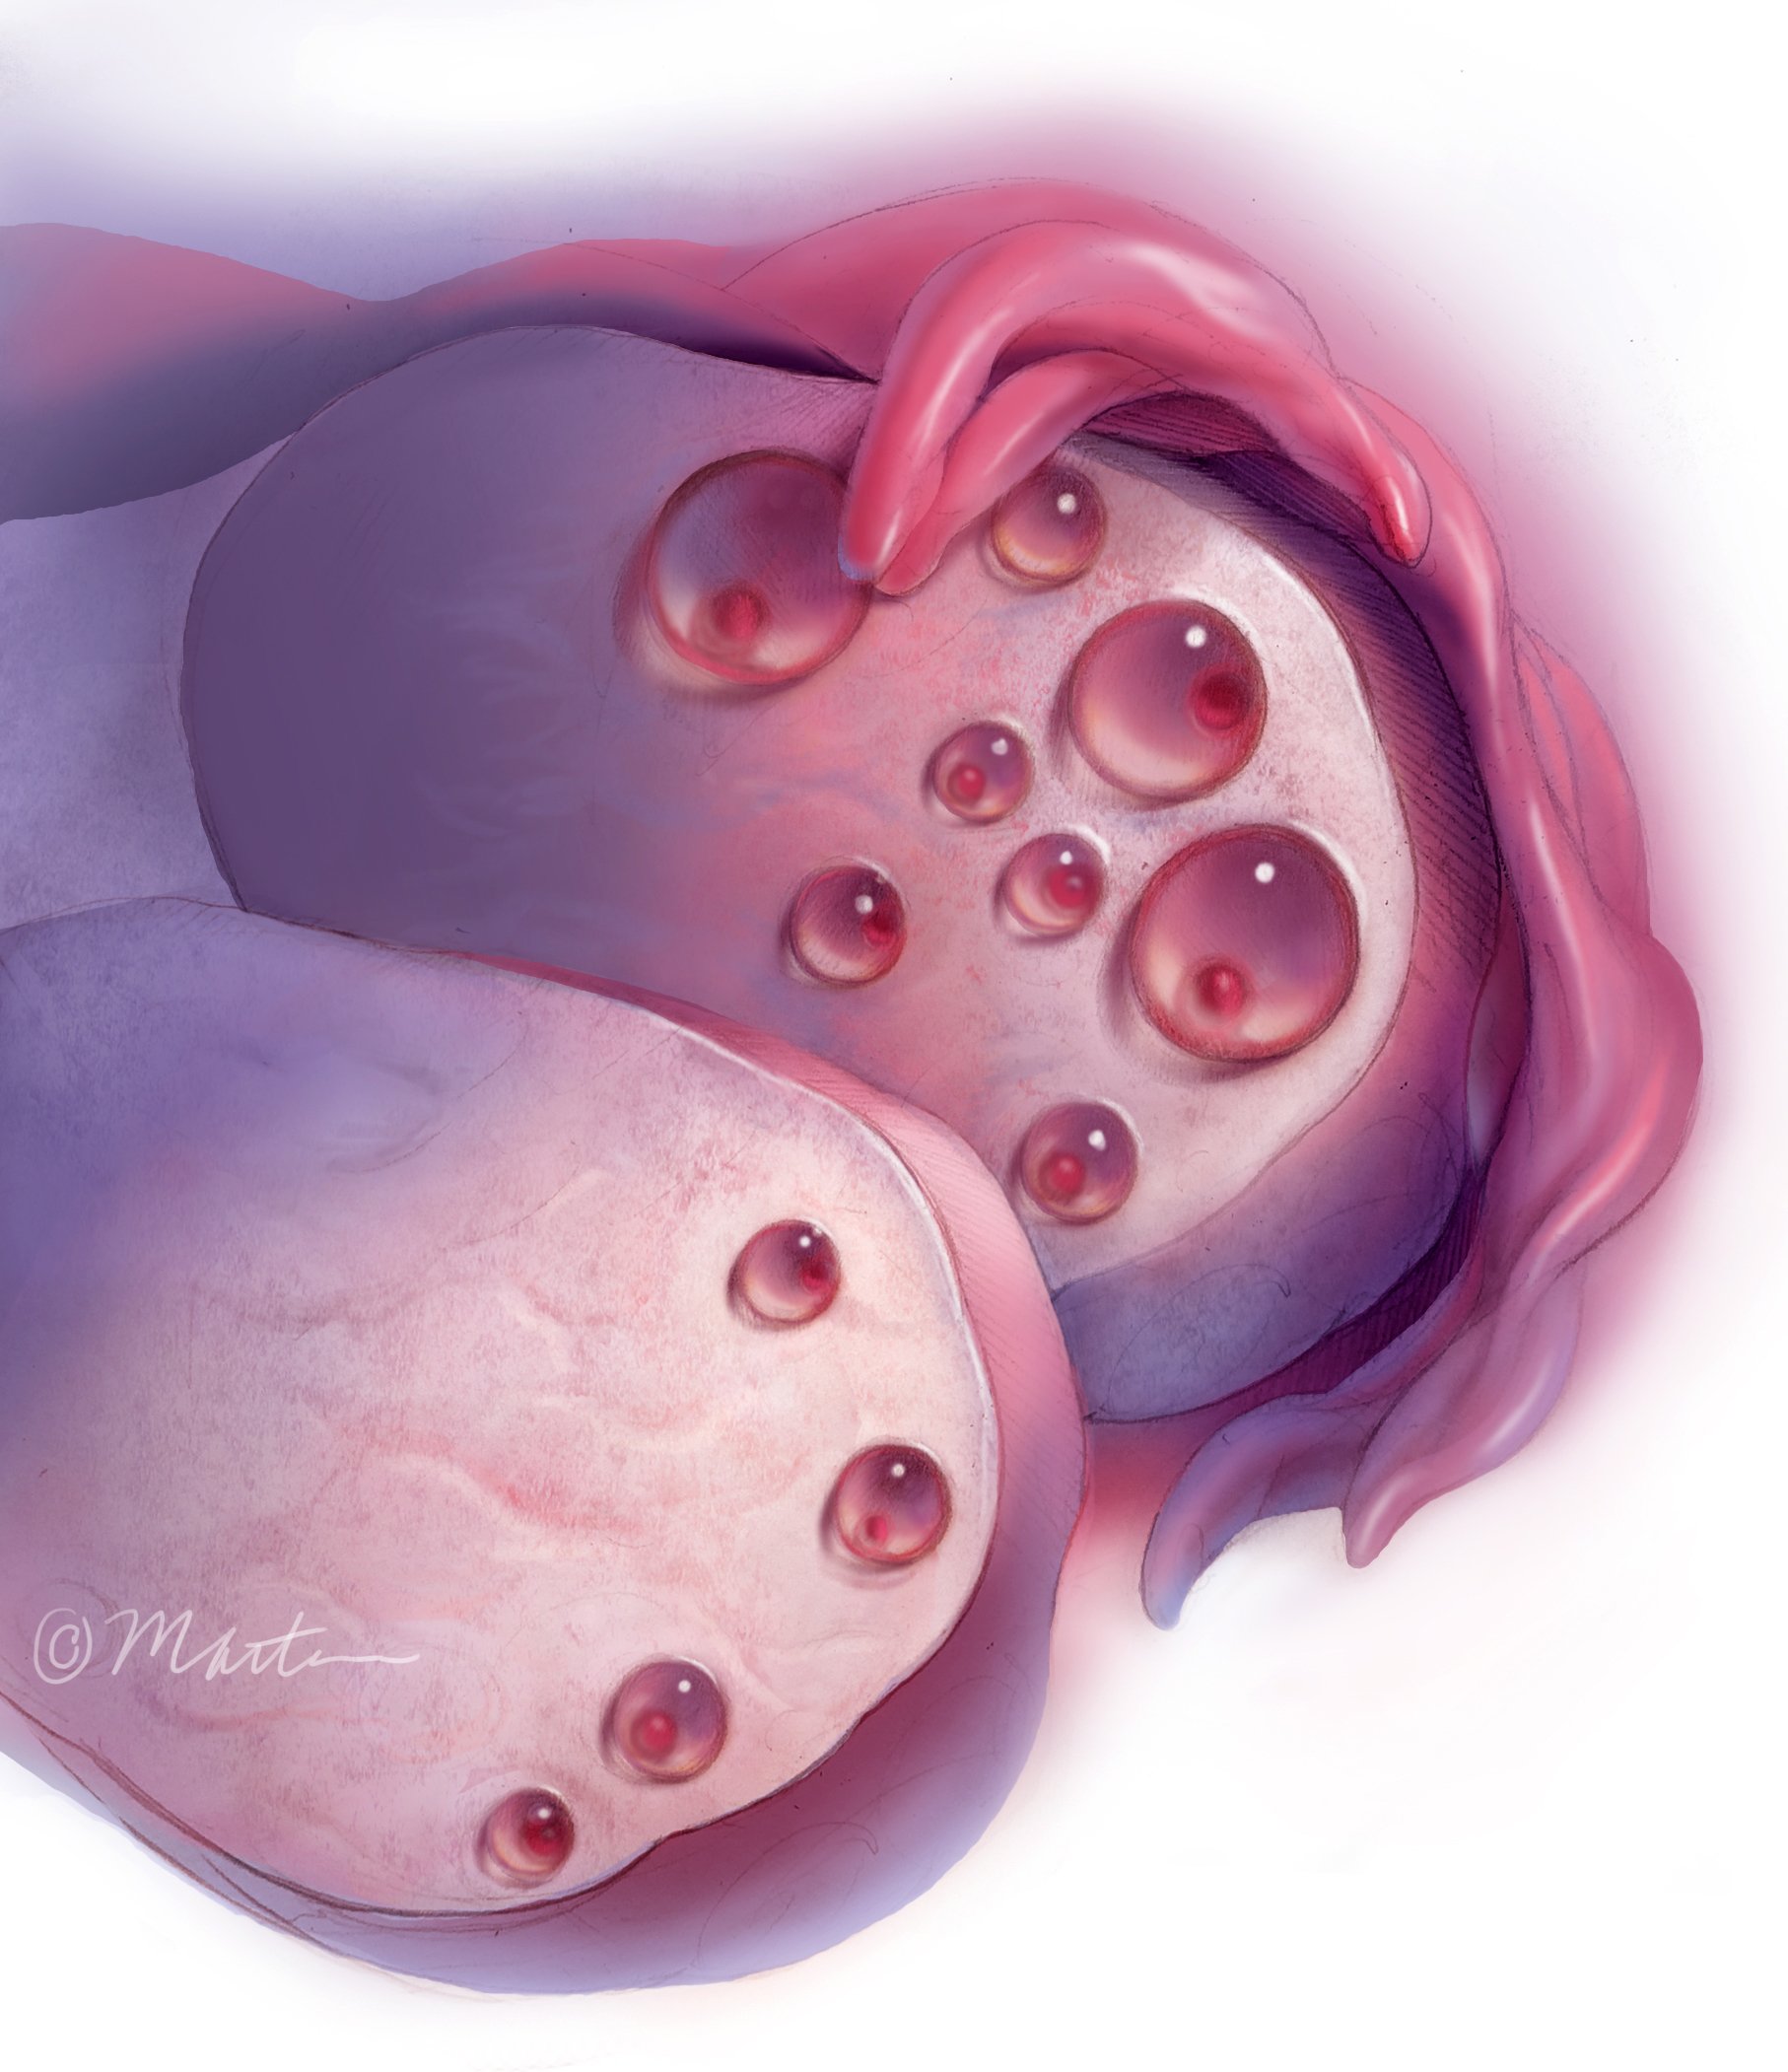

Follicle Count